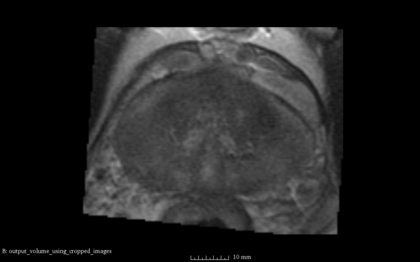

- the following images are shown from left to right:

- [1] Fixed Volume as Reference [2] SimpleITK result after Initialization [3] SimpleITK result after rigid registration [4] BRAINSFit result after rigid without using masks and --useCenterOfGeometryAlign